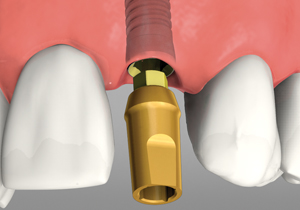

Anatomy Of Implant

An Abutment On The Implant